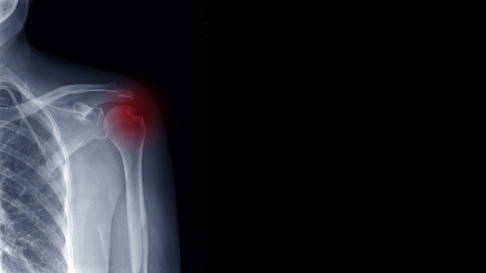

Bildgebende Diagnostik

Röntgenbilder von mehreren Seiten der Schulter ermöglichen dem Arzt zu beurteilen, ob Knochenteile verschoben sind und wie komplex der Bruch ist. Vor allem bei schweren Unfällen ergänzt die Computertomografie (CT) die Diagnostik. Das Verfahren hilft dem Orthopäden, komplexe Verletzungen des Schultergelenks und des Schulterblatts zu erkennen.